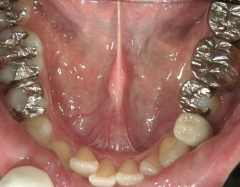

矯正歯科 治療後

矯正_灰色.pngno.28_6958_治療後_下.jpg矯正_灰色.png